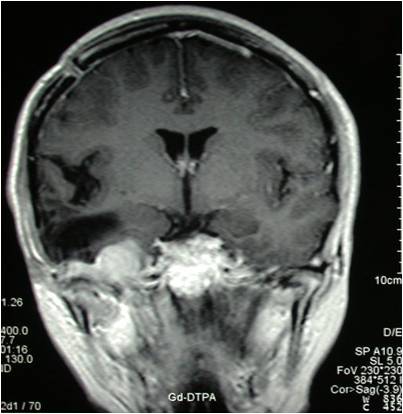

巨大中颅底脑膜瘤切除术

术前冠状位见右侧中颅底巨大占位